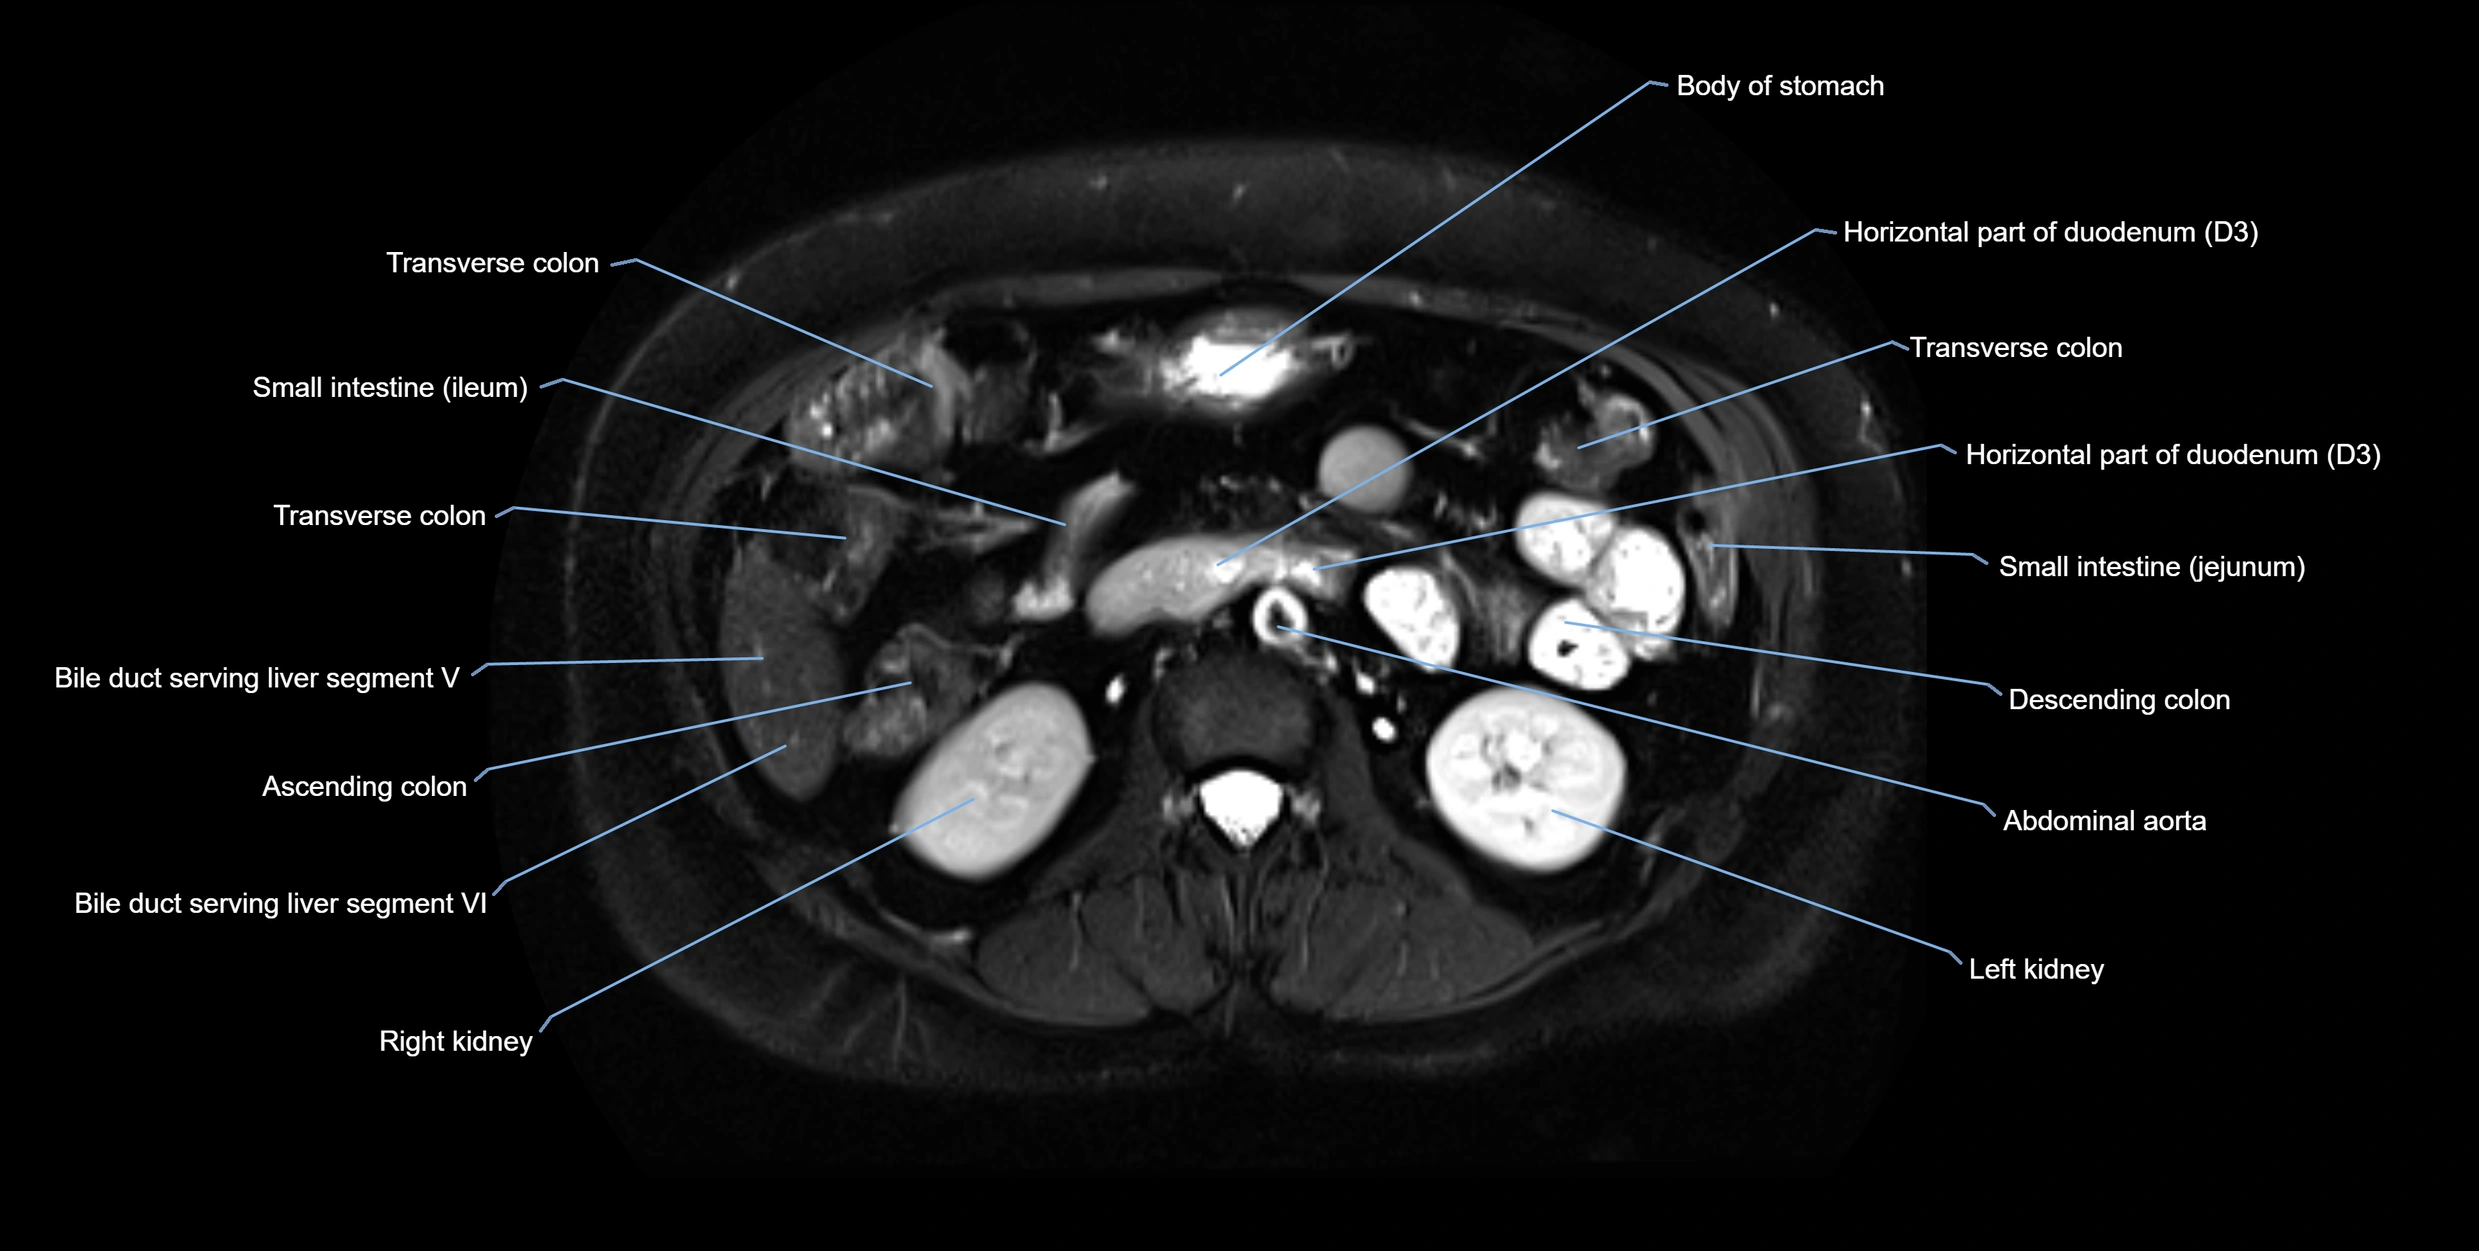

MRI image

image

Fullscreen Image